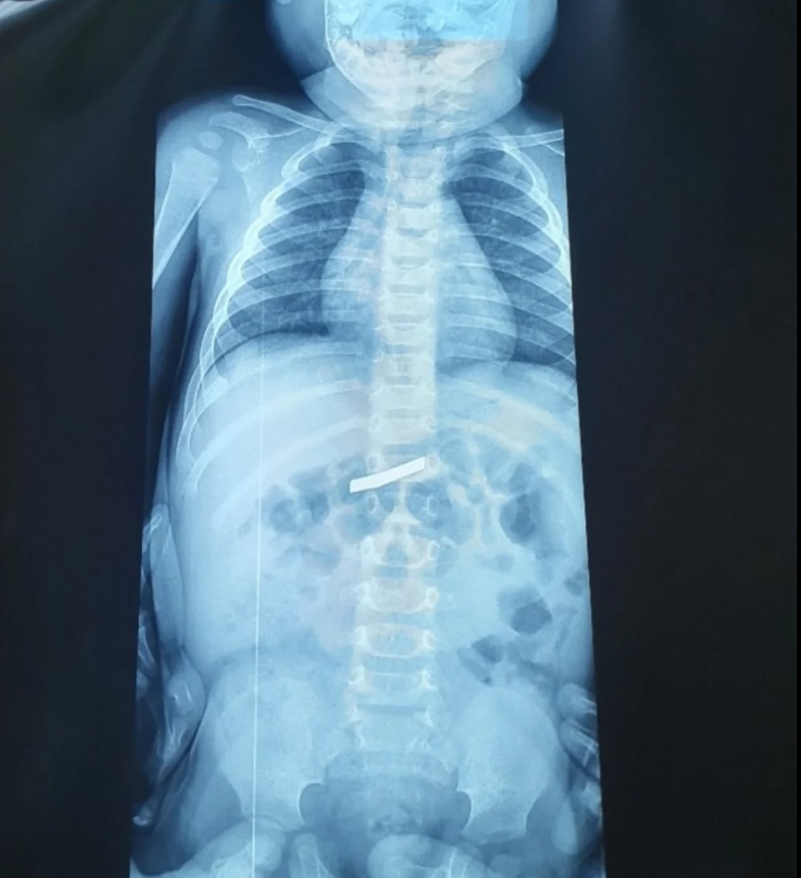

Ένας 3χρονος μεταφέρθηκε εσπευσμένα στο νοσοκομείο, το οποίο κατάπιε ένα ξυραφάκι. Το παιδί αφού έφτασε σε Παίδων της Αθήνας, υποβλήθηκε άμεσα σε ακτινογραφία, η οποία έδειξε ότι όντως υπήρχε το αιχμηρό αντικείμενο στο στομάχι του. Όπως ενημέρωσαν οι γιατροί, τους γονείς του παιδιού, μετά την ακτινογραφία προσδιορίστηκε και το ακριβές σημείο όπου βρέθηκε το ξυραφάκι, ώστε οι χειρουργοί να προχωρήσουν σε επέμβαση αφαίρεσής του με ασφάλεια. Η χειρουργική ομάδα προχώρησε άμεσα στη διαδικασία αφαίρεσης, μια επέμβαση που απαιτούσε λεπτούς χειρισμούς ώστε να αποφευχθεί οποιοσδήποτε τραυματισμός στα τοιχώματα του στομάχου ή του οισοφάγου κατά την εξαγωγή του αιχμηρού αντικειμένου. Παρά την πολυπλοκότητα και το υψηλό ρίσκο της κατάστασης, η έκβαση της επέμβασης ήταν απόλυτα επιτυχής. Οι γιατροί κατάφεραν να αφαιρέσουν το ξυραφάκι χωρίς επιπλοκές. Το μικρό αγόρι, μετά την ολοκλήρωση της διαδικασίας, μεταφέρθηκε σε θάλαμο νοσηλείας όπου και αναρρώνει πλέον υπό τη συνεχή επίβλεψη των ειδικών. Η έκβαση της επέμβασης ήταν επιτυχής και το μικρό παιδί αναρρώνει στο νοσοκομείο.

Σε ανάρτησή της η παιδίατρος Αρετή Μανιώτη δίνει στους γονείς συμβουλές για τις πρώτες βοήθειες αντιμετώπισης αυτού του δύσκολου περιστατικού. Όπως εξηγεί «Η κατάποση ξένου σώματος είναι αρκετά συχνή στις μικρές ηλικίες, όμως όταν πρόκειται για αιχμηρό αντικείμενο, όπως ένα ξυραφάκι, πρόκειται για επείγουσα κατάσταση. Το πρώτο βήμα είναι πάντα να δούμε πού βρίσκεται, με ακτινογραφία τραχήλου, θώρακα και κοιλίας. Αν είναι στον οισοφάγο, η αφαίρεση πρέπει να γίνει άμεσα με ενδοσκόπηση. Ακόμα όμως κι αν έχει φτάσει στο στομάχι, πάλι δεν το αφήνουμε στην τύχη του — λόγω του σχήματός του, συνήθως προχωράμε σε ενδοσκοπική αφαίρεση όσο πιο γρήγορα γίνεται. Αν έχει ήδη περάσει πιο κάτω στο έντερο, τότε μπαίνουμε σε στενή παρακολούθηση, με επανεκτιμήσεις και οδηγίες στους γονείς για συμπτώματα που δεν πρέπει να αγνοηθούν, όπως πόνος στην κοιλιά, εμετοί, αίμα ή πυρετός. Σημαντικό: δεν προκαλούμε εμετό και δεν δίνουμε τροφή με σκοπό να “σπρώξει” το αντικείμενο»